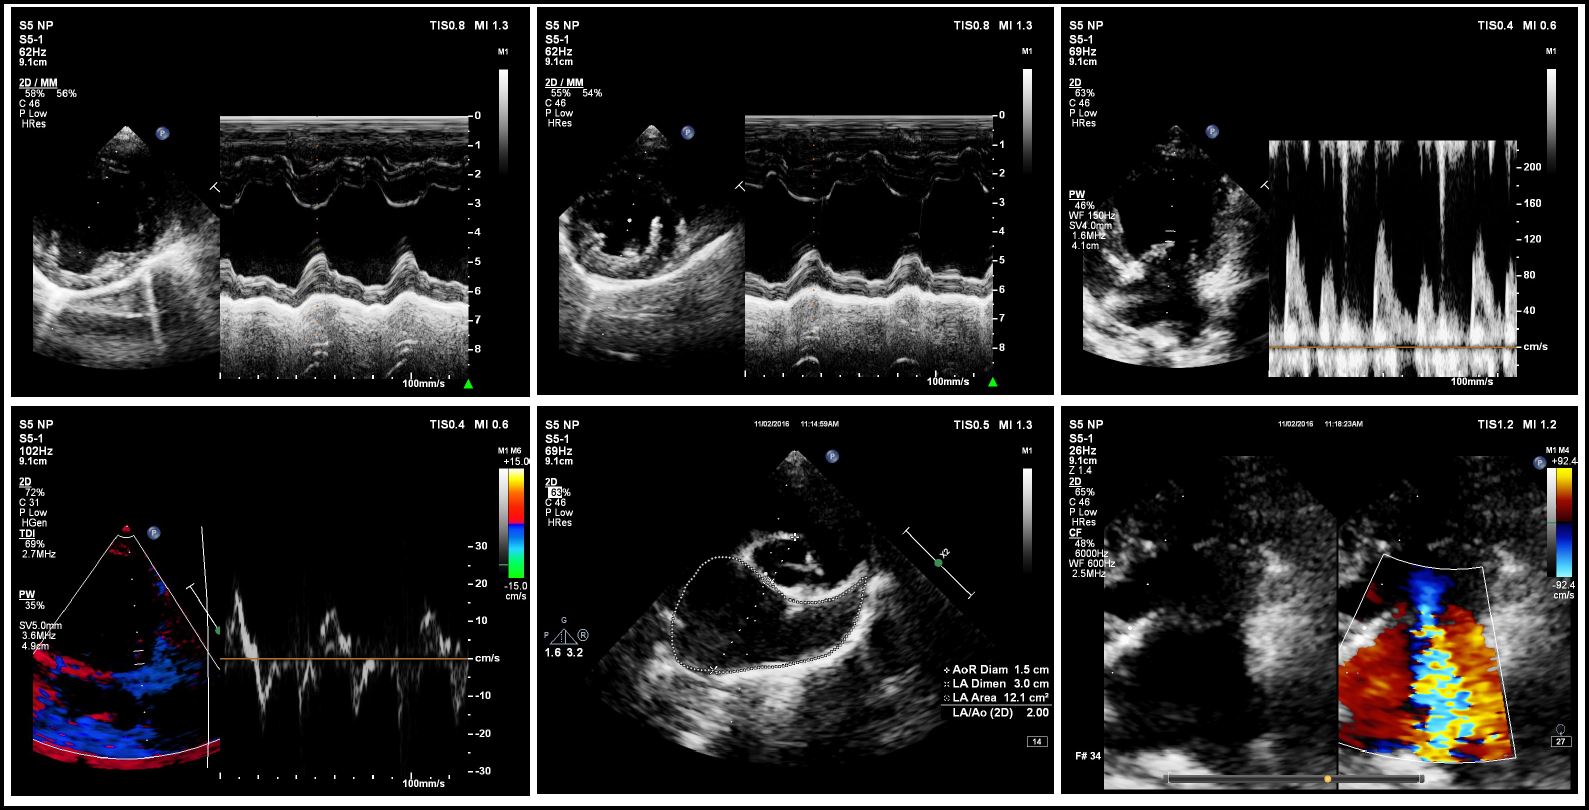

Zoey’s one year checkup was done October 28th 2017.  Zoey’s cardiologist (Dr. Hodge) was a bit worried Zoey’s left ventricle and left atrium (LV/LA) numbers were increasing after each checkup.  According to Dr. Hodge, Zoey’s pressure and her regurgitation were…